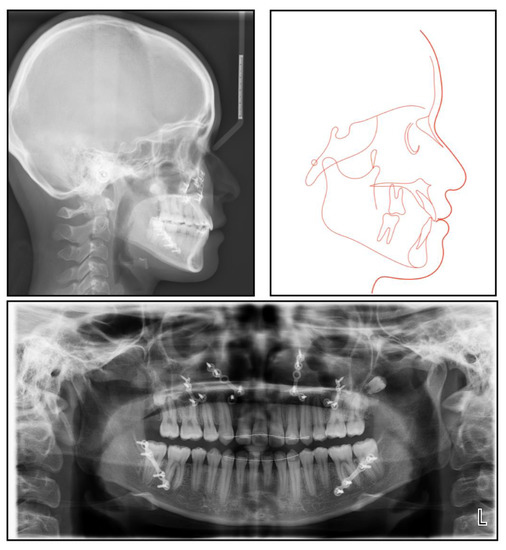

The panoramic radiograph showed that both the maxillary canines and all the third molars were impacted, and no significant periodontal support loss was found. The cephalometric analysis (Figure 3 and Table 1) showed a severe skeletal Class III relationship (ANB, −4.0°) with an insufficient developed maxilla (SNA, 77.2°). The maxillary incisors were relatively well-positioned, while the mandibular incisors were lingually inclined (U1-SN,104°; L1-MP, 86.5°) [8].

The final panoramic radiograph confirmed parallel roots with no apparent root resorption. Cephalometric analysis (Figure 9 and Table 1) indicated a normal anteroposterior (AP) relationship (ANB, from −4° to 1.3°) and decreased lower third (FMA: from 26.6° to21.5°; Na-Me: from 111.8 mm to 103.7 mm). Furthermore, the distance from the upper and lower lips to the E-line were significantly decreased, which helped improve the soft tissue profile.

Figure 3. A pretreatment lateral cephalometric radiograph and tracing and a panoramic radiograph.

Figure 9. Posttreatment lateral cephalometric radiograph and tracing and a panoramic radiograph.